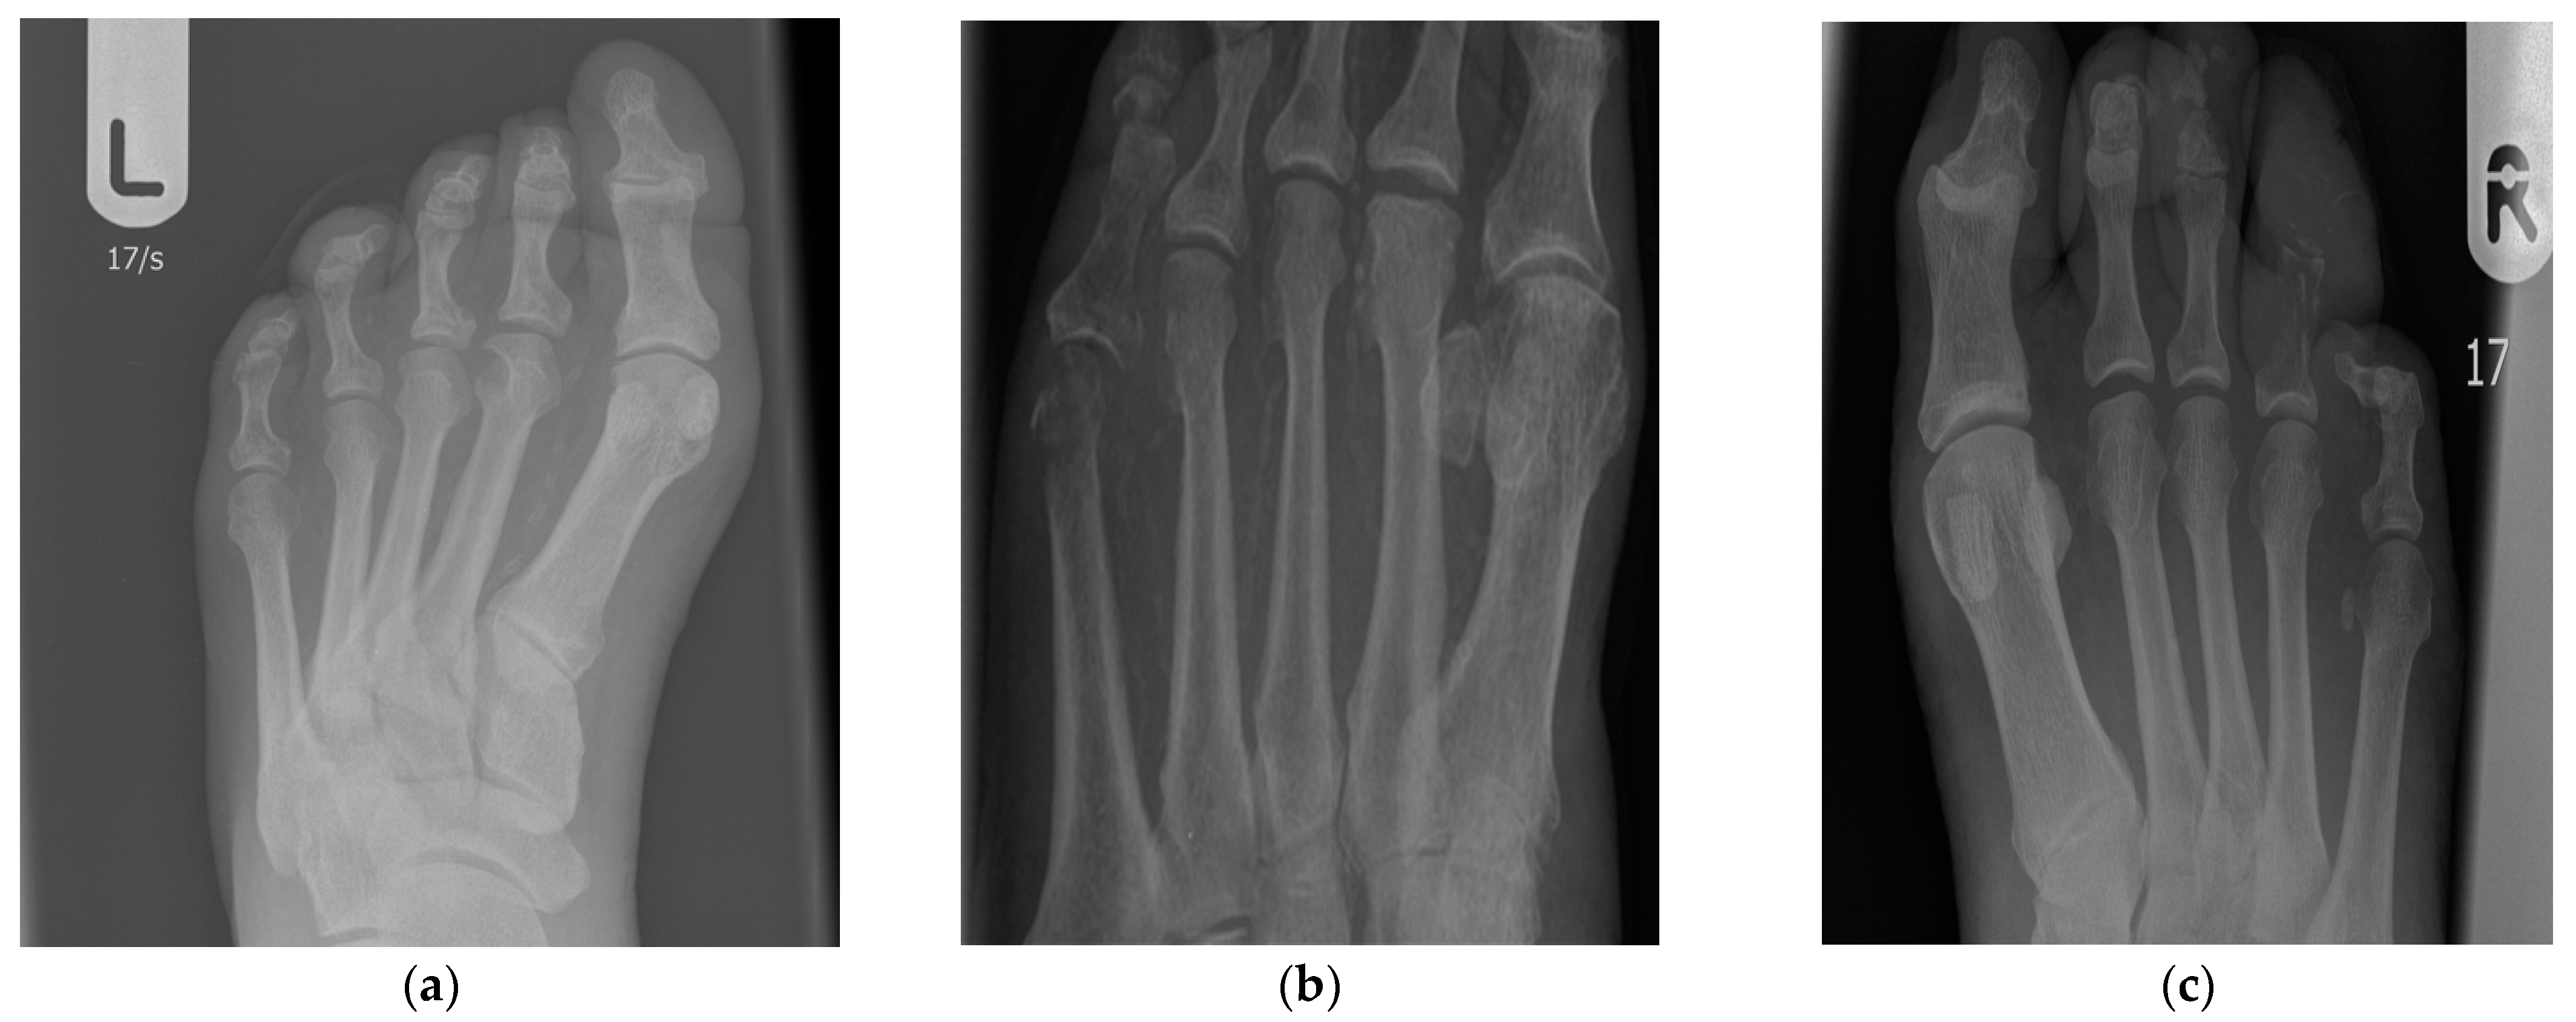

4.4. Osteitis and X-ray Evaluation

- Aragón-Sánchez, J.; Lipksy, B.; Lázaro-Martínez, J. Diagnosing diabetic foot osteomyelitis: Is the combination of probe-to-bone test and plain radiography sufficient for high-risk inpatients? Diabet. Med. 2011, 28, 191–194. [Google Scholar] [CrossRef]

- Lipsky, B. Osteomyelitis of the foot in diabetic patients. Clin. Infect. Dis. 1997, 25, 1318–1326. [Google Scholar] [CrossRef]

- Kothari, N.A.; Pelchovitz, D.P.; Meyer, P.J. Imaging of musculoskeletal infections. Radiol. Clin. N. Am. 2001, 39, 653–671. [Google Scholar] [CrossRef]